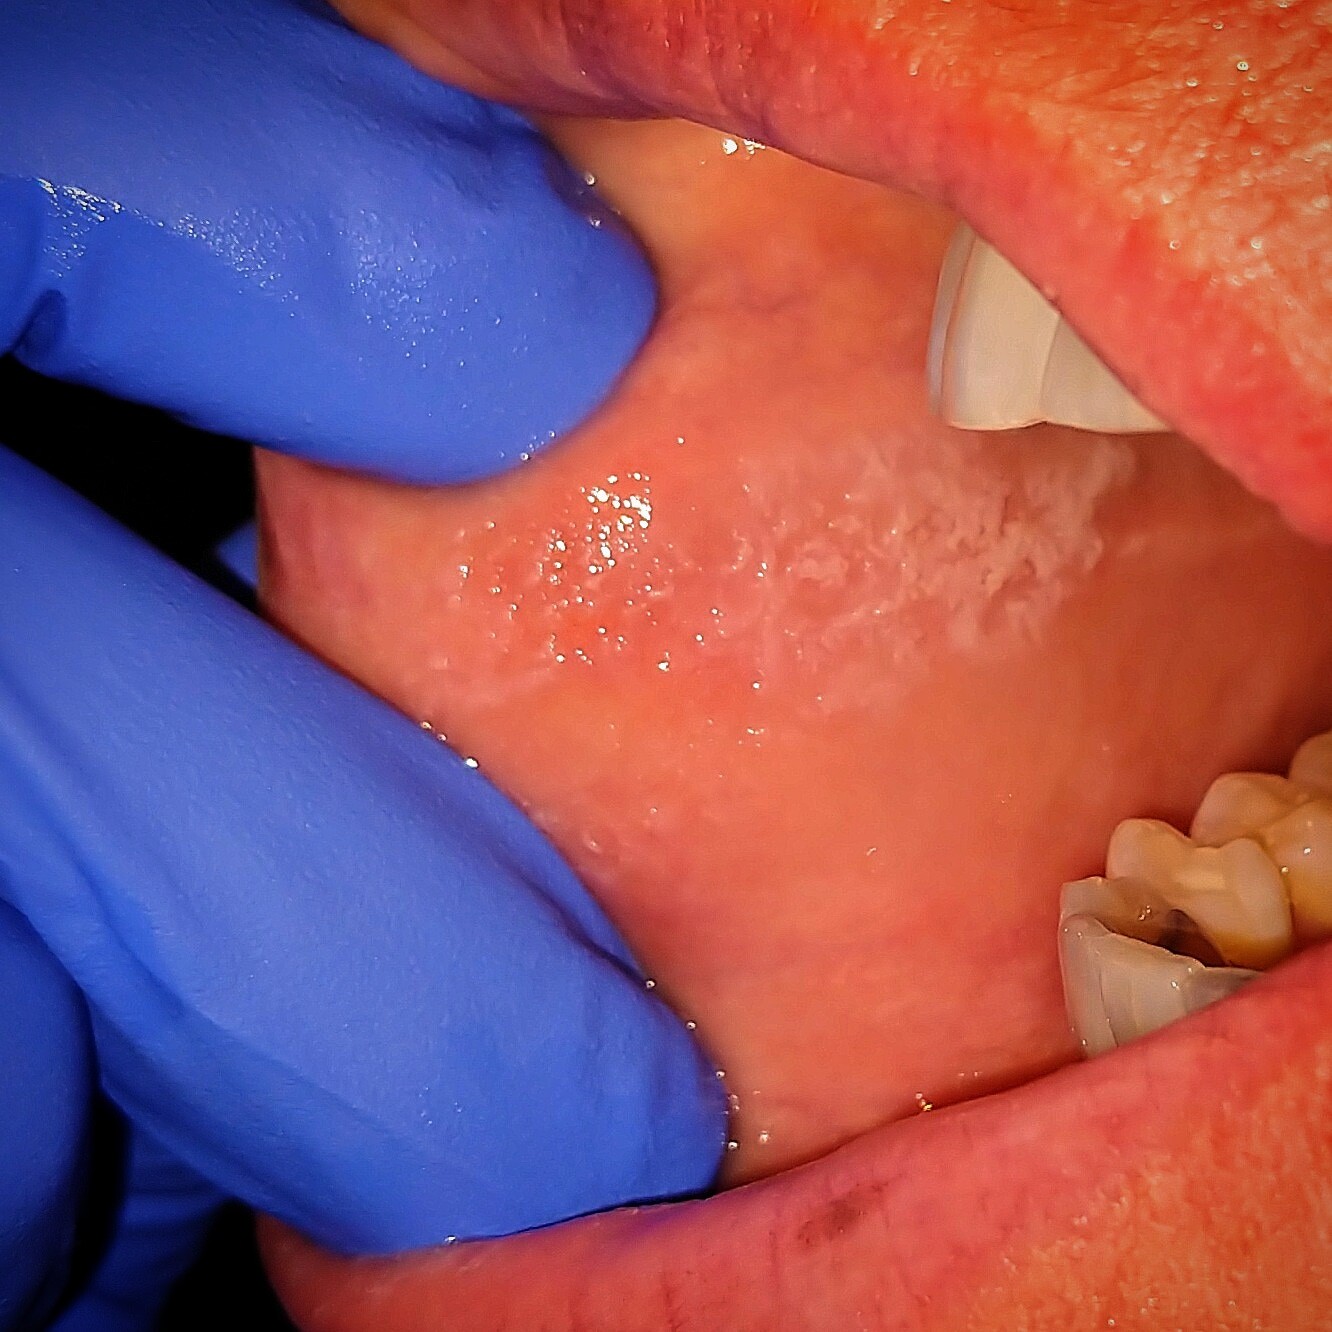

Psychological-related biting. Chronic cheek biting (known as morsicatio buccarum) is a compulsive behavior that repeatedly causes someone to bite the inside of their cheek. It's classified as a body-focused repetitive behavior (BFRB). In some cases, someone with BFRB might not even be aware that they're biting their cheek.

Chronic cheek biting can result in redness, painful sores, and tears in the mouth's inner lining (known as the mucosa). With BFRB-related cheek biting, you might also feel increased guilt, shame, or hopelessness, or shy away from social activity to prevent others from noticing the biting.